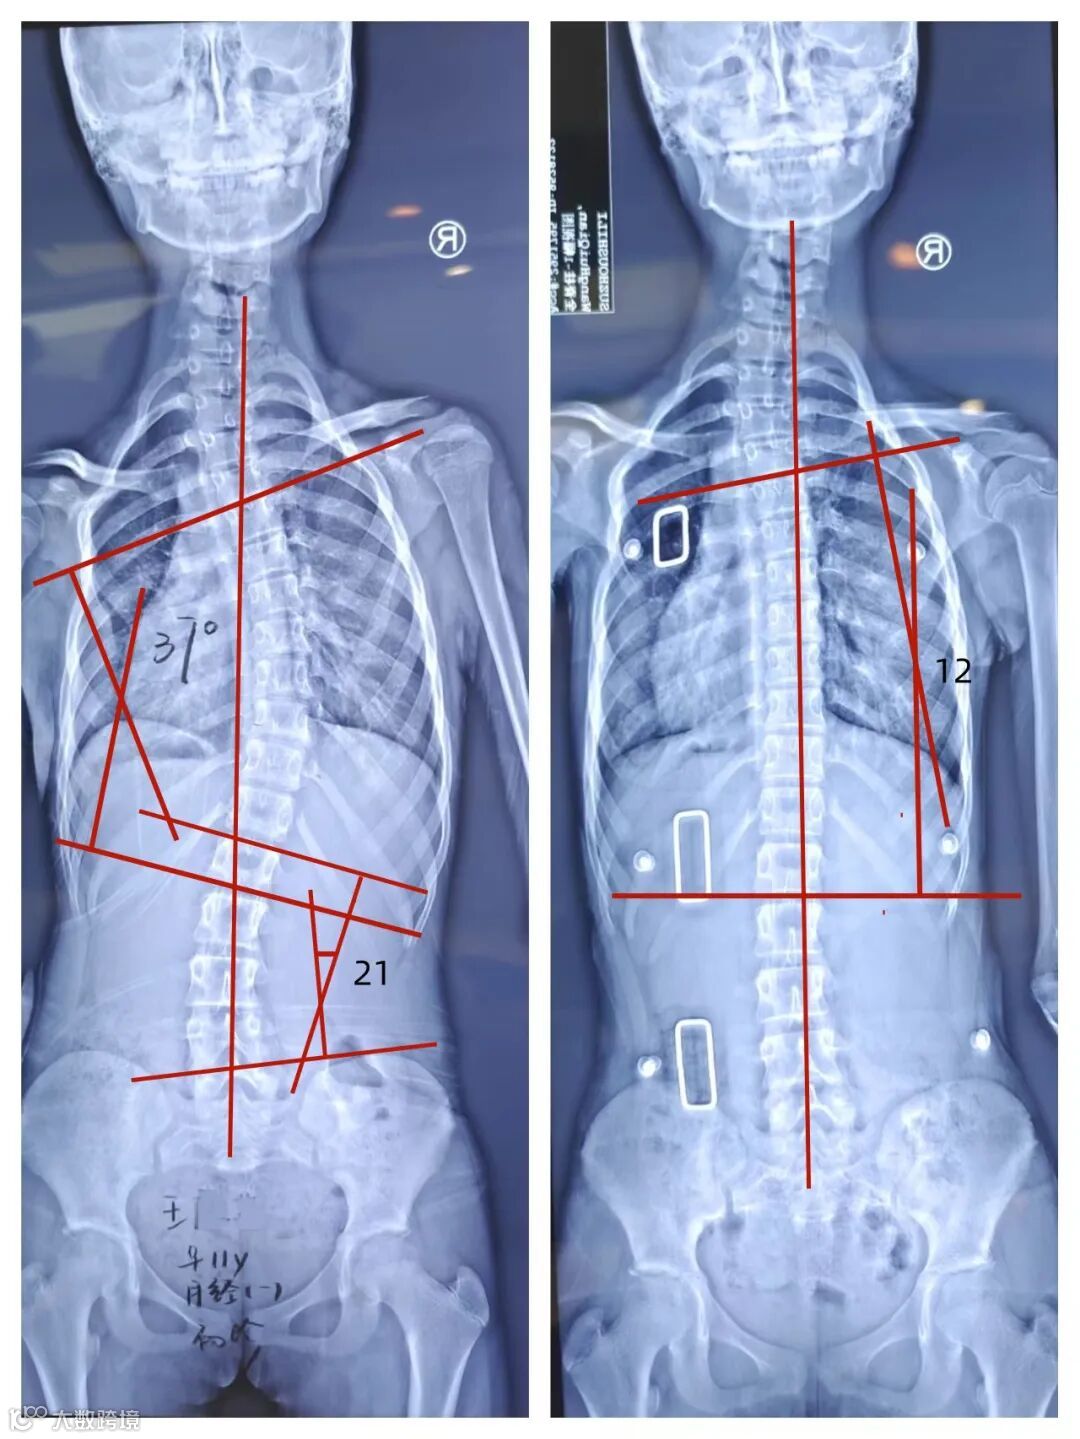

王同学,女,11岁,6年级,在一次学校的集体筛查中发现双肩不等高,Adam实验剃刀背明显,家长带孩子随向医院拍片发现脊柱侧弯,穿戴前首次制作支具前评估:胸段Cobb角37°,腰段Cobb角21°,椎体旋转度Ⅲ度,Risser症Ⅲ度,月经来潮1年,高低肩明显。

穿上支具经过一周适应期后复查:胸段Cobb角12°,腰段Cobb角10°以内,(因颈椎段侧凸位置较高矫正受限)由于孩子家长比较重视且孩子配合度比较高每天穿戴20小时以上,矫正效果明显。

穿戴前 穿戴后